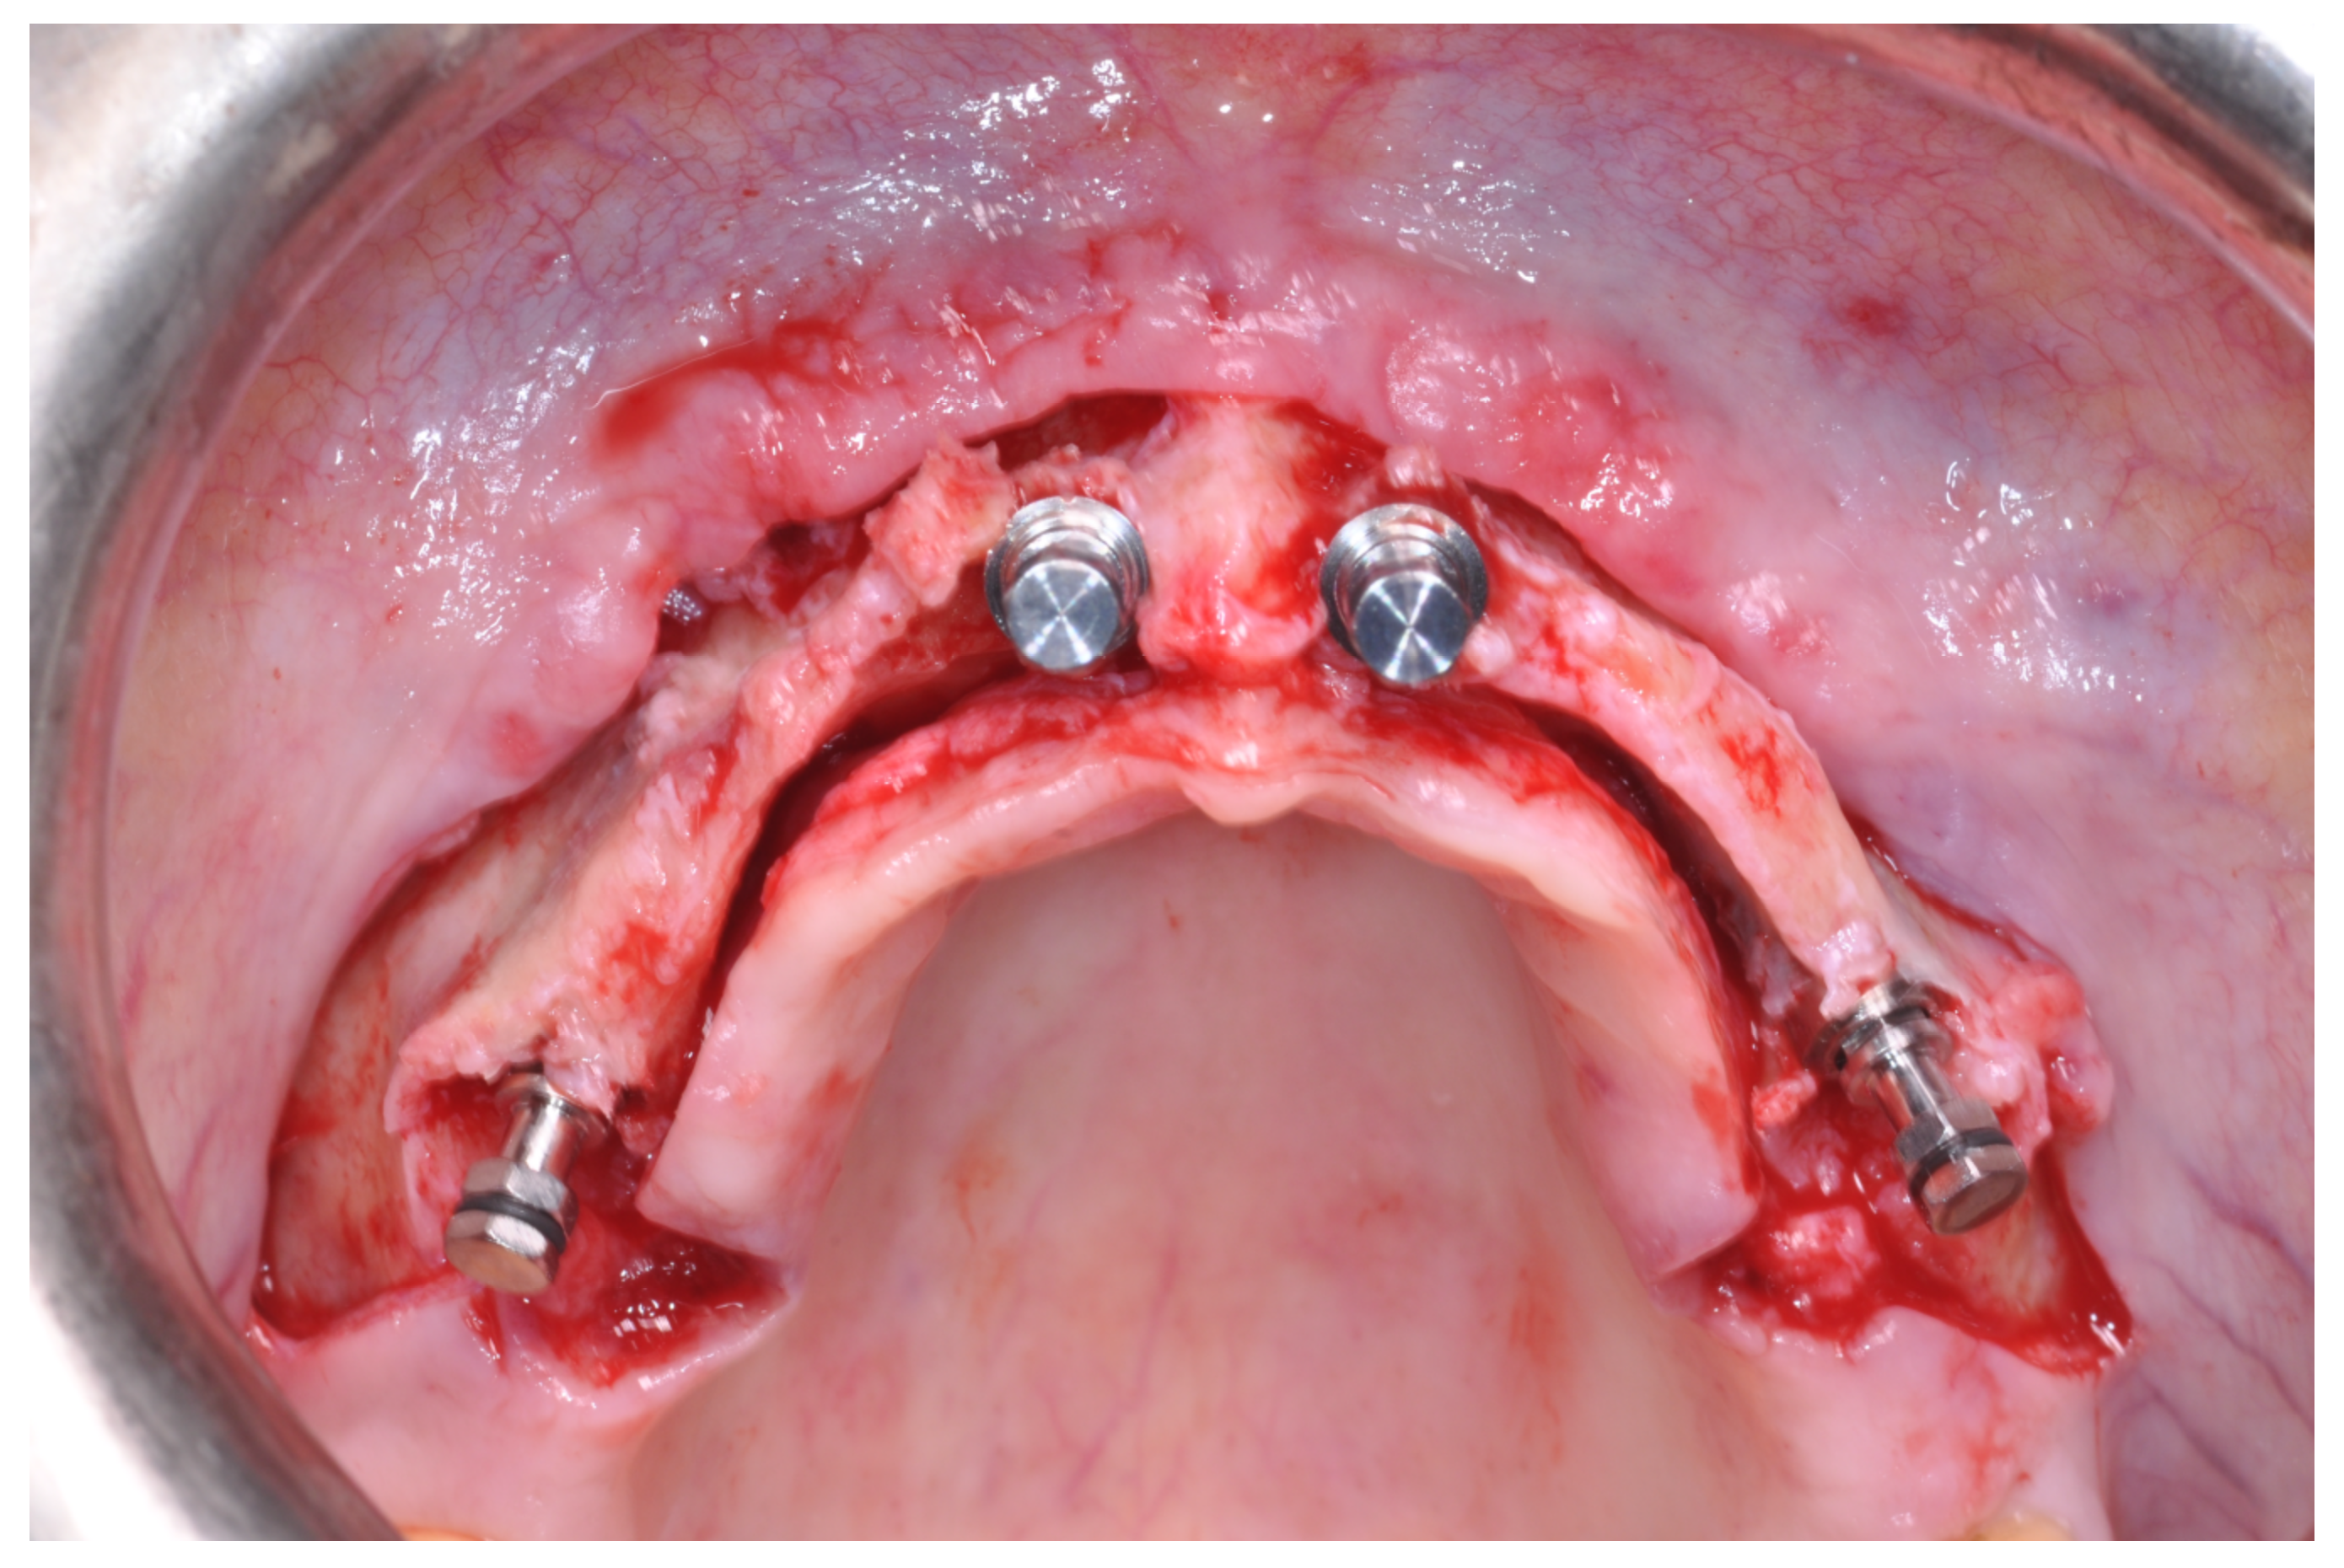

Patients rinsed with a chlorhexidine mouthwash (0.2%) for 1 min immediately prior to the intervention. Local anesthesia were administered using mepivacaine with adrenaline at ratios of 1:100,000 or 1:50,000. Crestal incisions were made with releasing incisions far away from the future membrane positioning and full thickness flaps were elevated. After the meticulous removal of all residual soft tissues in the regenerating site, copious bleeding was induced using a bone scraper (Safescraper Curve TWIST, META, Reggio Emilia, Italy) (Figure 1). A prosthetically guided implant placement was performed following the instructions of manufacturer (Thommen Medical, Grenchen, Switzerland). Only 1 patient had implants placed 9 months after bone augmentation because the initial bone thickness did not permit the primary stabilization of the implant fixtures (Figure 2, Figure 3, Figure 4, Figure 5, Figure 6, Figure 7 and Figure 8).

Figure 1. Graft recipient area after bone decorticalization and distal fixation of the non-resorbable barrier.

Figure 4. Placement of the graft and of the non-resorbable membranes, fixed with pins.

Figure 7. Placement of the dental implants.

At this point, a non-resorbable high-density PTFE barrier (Cytoplast TXT-200, Osteogenics Biomedical, Lubbock, TX, USA) was designed on the basis of the bone defect shape and was distally blocked on the bone by two titanium pins (Kalos, Nike, Orbetello, Italy). A mixture of 50% autogenous bone harvested from the mandibular ramus with the use of a scraper and 50% inorganic bovine bone (Bio-Oss, Geistlich, Wolhusen, Switzerland) was placed in the recipient site and the membrane was pulled and blocked on the bone with two mesial pins. With this particular, and innovative, non-resorbable membrane management, the graft was compressed and fixed on the recipient bed (Figure 9, Figure 10 and Figure 11). The occlusal portion of the graft was then covered with a layer of a collagen resorbable barrier (Bio-Gide, Geistlich) (Figure 12) and peri-osteal incisions were performed to make the flap passive.

Figure 9. Occlusal view after implant placement.